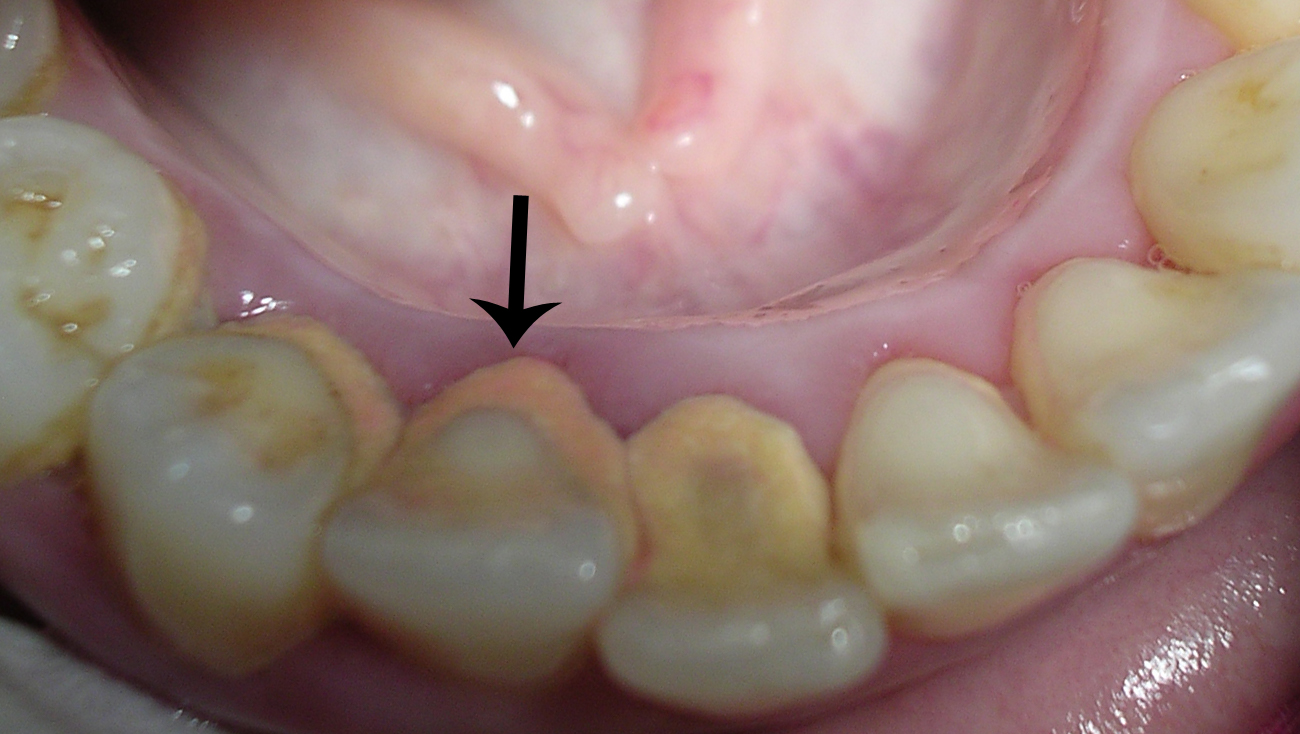

Fogkő eltávolítás – a nulladik lépés!

Az Apollonia Dental Centerben minden kezelés a fogkő szakszerű eltávolításával kezdődik. Ebben a bejegyzésben azt járjuk körbe, hogy miért is van erre szükség, valamint, milyen panaszokat okozhat a fogkő.